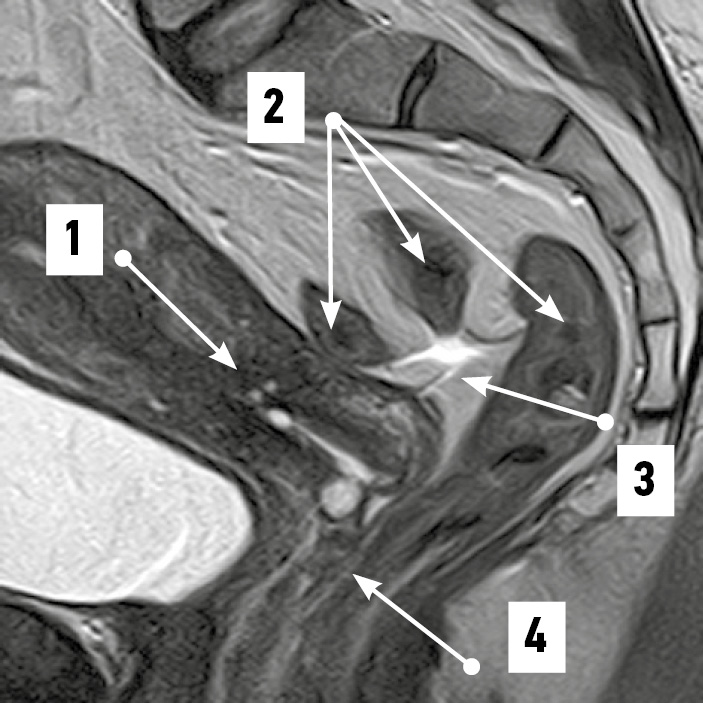

Рис. 2. Изгиб надвлагалищного участка прямой кишки, соответствующий тазовой поверхности крестца. Магнитно-резонансная томограмма органов таза в режиме SG T2: 1 — матка; 2 — прямокишечно-маточное пространство; 3 — надвлагалищный участок прямой кишки, соответствующий вогнутости крестца; 4 — влагалищный участок прямой кишки. / Fig. 2. Convolution of the supravaginal segment of the rectum, corresponding to the pelvic surface of the sacrum. SG T2-magnetic resonance imaging of pelvic organs: 1 — uterus; 2 — rectal–uterine space; 3 — supravaginal segment of the rectum corresponding to the sacrum concavity; 4 — vaginal segment of the rectum.

По результатам МРТ-анализа при положениях матки anteversio-anteflexio надвлагалищный участок прямой кишки в половине случаев (52,4%) был извит во фронтальной плоскости (рис. 1). В 38,1% случаев кишка имела ход, соответствующий вогнутости крестца (рис. 2), ещё в 9,5% сагиттальный изгиб кишки был значительно выражен. Расстояние между маткой и прямой кишкой в надвлагалищном участке в среднем составило 5,93±0,97 мм. Здесь прослеживался значительный разброс минимальных и максимальных величин, свидетельствовавший о разнообразии положения органов: от их крайней степени близости — 0,00 мм (рис. 3) до удалённого положения — 17,00 мм (рис. 4). Последнее может служить анатомической предпосылкой для положения петель тонкой кишки в относительно широком прямокишечно-маточном углублении.